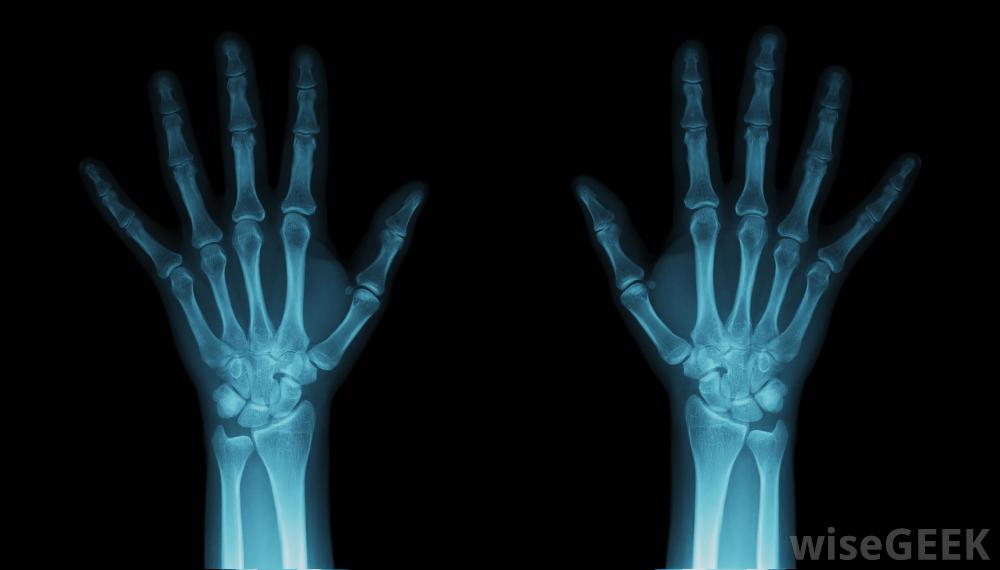

手腕韧带撕裂首先要经过医生的检查。为了了解损伤的程度,将对手腕进行x光或磁共振成像(MRI)扫描。如果不能得到清晰的图像、关节镜或微型摄像机,可能会被插入腕关节。医生还会询问您以前的健康史以及您在同一关节上的任何损伤。

可能需要对手腕进行X光检查韧带损伤。